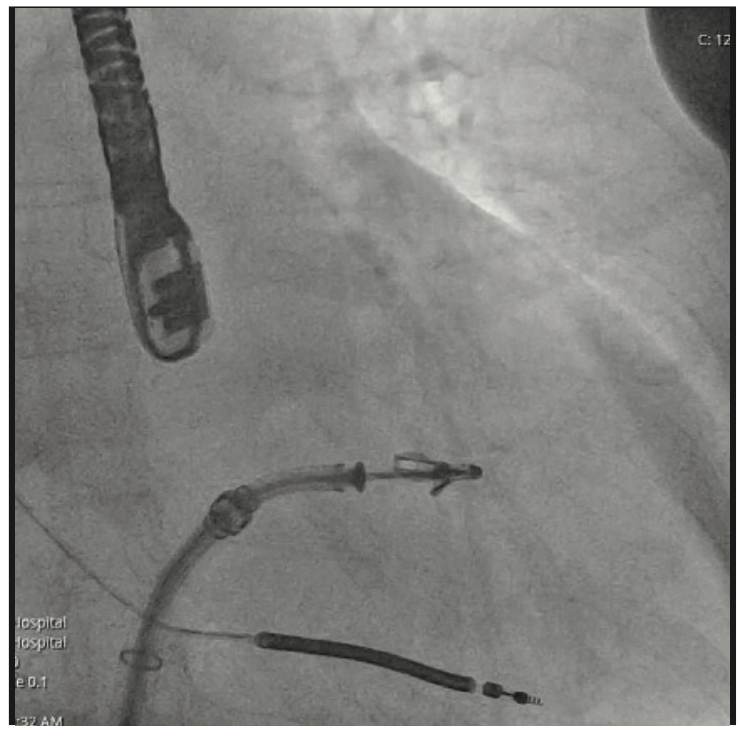

Crossing the interatrial septum was challenging. Although we were able to cross the interatrial septum with a transseptal needle, advancing the sheath across the fossa ovalis was difficult. Several maneuvers such as rotating and redirecting the sheath were not successful. Pre-dilation of the septum with 5 mm x 40 mm balloon did not allow for insertion of the MitraClip guide across the interatrial septum. At this point, we elected to use the balloon-assisted tracking (BAT) technique. Using a 7 mm x 40 mm balloon that was inflated to 10 atmospheres (atm) at the tip of the guiding catheter, we were able to advance the sheath through interatrial septum (Figures/Videos 1-3). Subsequently, a G4 XTW MitraClip was successfully deployed in the central position. A post procedure transesophageal echocardiogram showed mild mitral regurgitation.

Video 2. Sheath entering through the interatrial septum.

Transseptal access is essential for many procedures including transcatheter mitral valve interventions, pulmonary vein isolation, left atrial appendage closure, and percutaneous left ventricular assist devices. However, there are many scenarios that one might face that can make transseptal access challenging. These include but are not limited to difficult engagement of the fossa ovalis, needle advancement, and sheath and guide advancement.1 In our case, MitraClip guide advancement was challenging. We were able to overcome this using the BAT or the ‘inchworming’ technique. This technique was originally described to overcome tortuosity, or a small-caliber or spastic radial artery during a transradial approach.2 We describe a new implication for the inchworming technique. The conical shape of the inflated balloon provides flexibility, minimizes trauma, and allows atraumatic transseptal access.